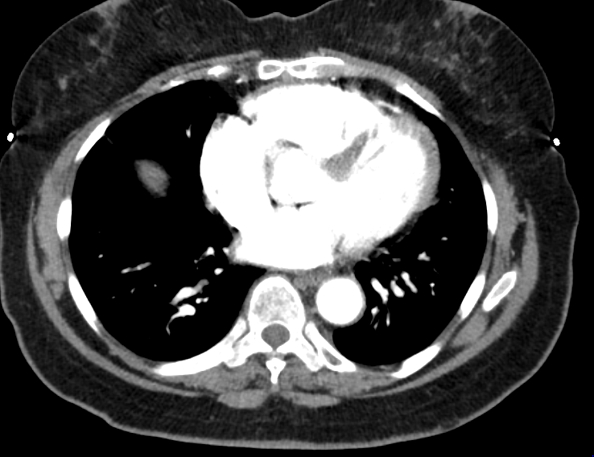

A 70-year-old woman with no cardiovascular history presented with sudden-onset, severe substernal chest pain radiating to the back while doing yard work, associated with diaphoresis, shortness of breath, and right-hand paresthesia. She was a never-smoker and denied alcohol or drug use. At urgent care, her blood pressure was 196/174 mmHg. After receiving aspirin and sublingual nitroglycerin, she was transferred to the ED with persistent back pain (BP 186/110 mmHg). D-dimer was 1.49. ECG showed no ischemia. CTA revealed a Stanford type B aortic dissection extending from the distal arch to the aortic hiatus. She was started on IV esmolol and nicardipine and transferred for vascular surgery evaluation. TTE showed normal LV ejection fraction (65–70%), grade 1 diastolic dysfunction, and moderate concentric LV hypertrophy. She was managed conservatively without surgery, transitioned to oral antihypertensives, and scheduled for surveillance follow-up to monitor for progression.

Initial labs showed elevated hemoglobin (18.2 g/dL) and hematocrit (58.9%), prompting outpatient evaluation. Hematologic workup revealed low erythropoietin (1.8 mIU/mL) and a positive JAK2 V617F mutation, confirming polycythemia vera. She was started on hydroxyurea, low-dose aspirin, and serial phlebotomy. Hematocrit and BP normalized, and repeat CTA at 3 months showed complete resolution of the dissection.